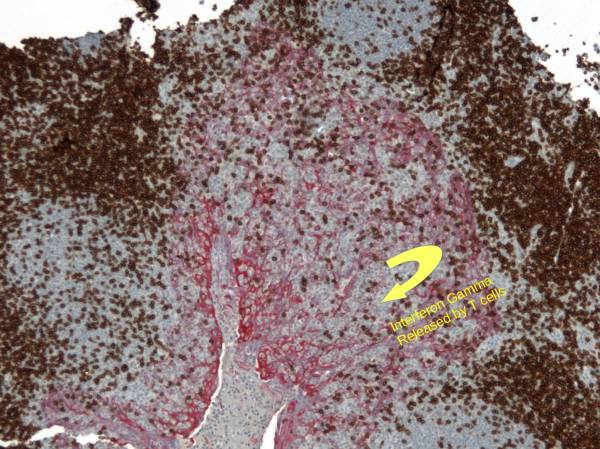

At low magnification (Left), one sees the heterogeneous expression of PDL1 in a tonsil which is used as a preferred positive on-slide control for PDL1. This expression is explained by a focal invasion of T cells reaching an infectious area (Center: DAB: CD3, RED: Cytokeratin). The T cells release Interferon-Gamma which stimulates local expression of PDL1 by the epithelium. The right picture shows PDL1 expression at higher magnification.